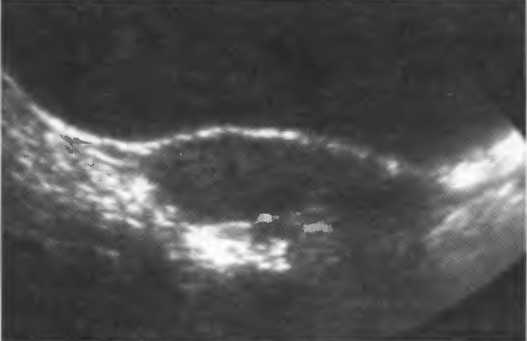

Кисты

Киста, как правило, визуализируется в виде анэхогенной зоны, при этом структуры, расположенные за кистой, обычно усилены: полость кисты анэхогенна, поскольку в ней нет структур с различным акустическим сопротивлением. В результате того что жидкость не поглощает ультразвук в такой же степени, что и ткань, эхо-сигналы от расположенных позади кисты структур гиперкомпенсированы сканером и выглядят усиленными — появляется эффект усиления задней стенки (рис. 14а,б).

Киста определяется в виде анэхогенной зоны с усилением по задней стенке. Если в кисте есть внутренние зхоструктуры, то они могут быть реальными или являться артефактами.

Рис. 14а. Заполненная жидкостью киста: полость кисты анзхогенна, имеется усиление задней стенки.

Рис.14б. Данная киста яичника имеет толстые стенки и внутренний осадок, создающий внутреннюю эхоструктуру, перемещающуюся при перемене положения тела пациента.